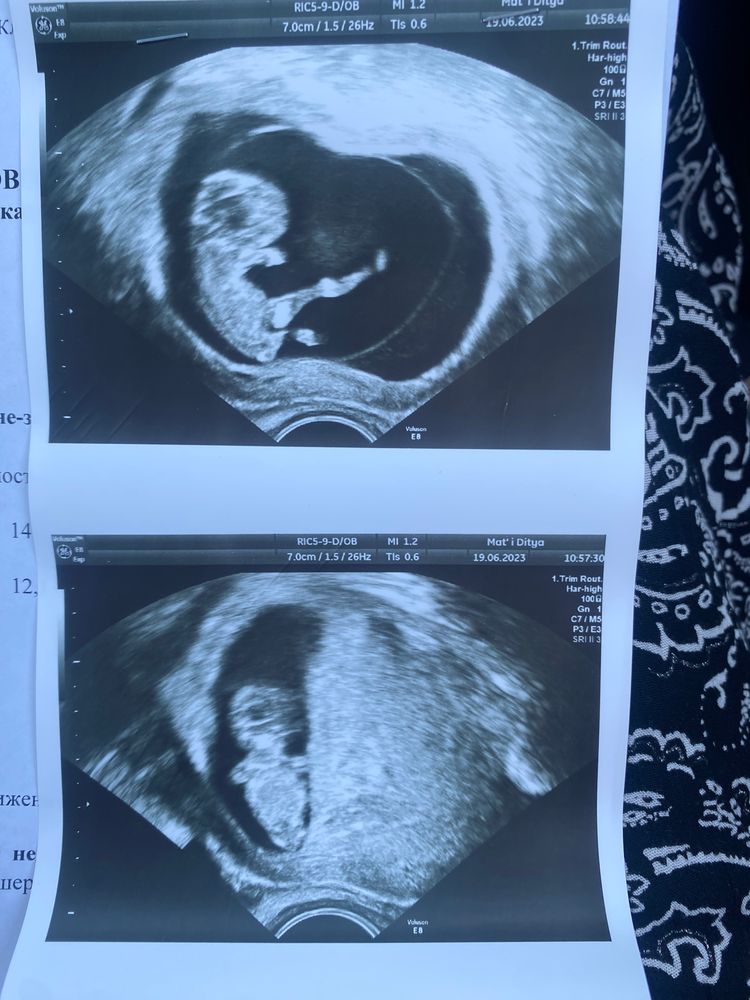

Всем здравствуйте! Сегодня ровно 10 недель. С мужем ходили на узи для себя. Очень активный ребенок, танцует во всю. И врач несколько раз оговорилась «крупный мальчик», «молодой человек». Когда спросила у неё: «мальчик?» она замешкался и сказала: «может и девочка, я так ляпнула просто». Может ли на таком сроке врач увидеть пол?

и фото прикладываю

Он на первой фотке как каратист замахнулся ногой вам😂

Слушайте, я не знаю как другие, а я на 1 фото увидела явный писюн к верху... у девочек этот орган в другую сторону направлен...я думаю узистка тоже это видела, но чётко говорить не стала, чтоб потом не быть виноватой, что ошиблась...

на 13 неделе мне четко на экране показывали половые органы сына. На фото ваших такого ракурса нет, да и рановато